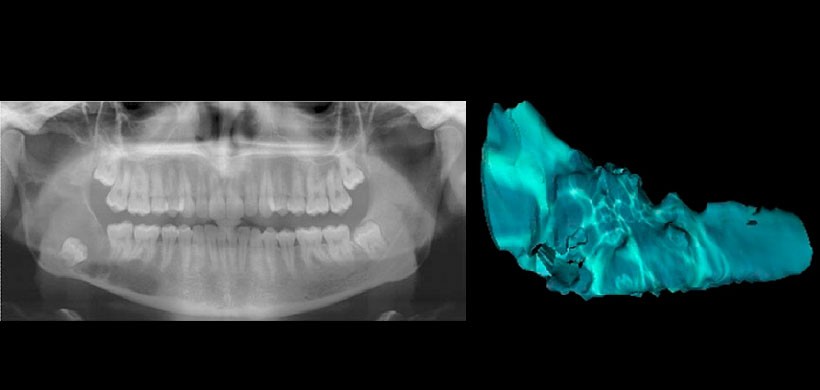

Fig 1. Radiografía panorámica y reconstrucción 3 D del volumen de la lesión, en un paciente con probable diagnóstico de tumor odontogénico queratoquístico que se va a someter a una descompresión quirúrgica.